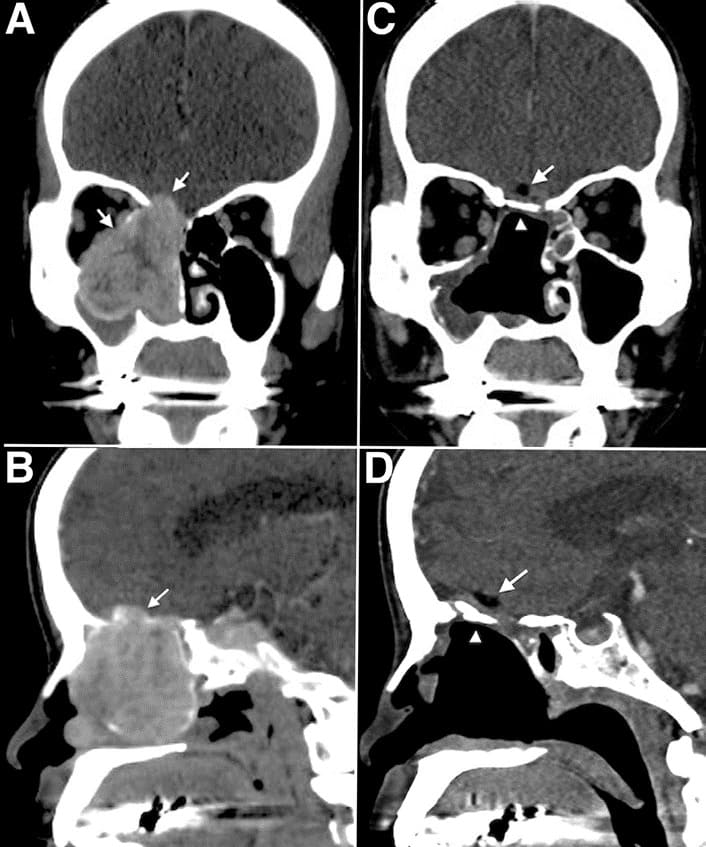

Figure 1: Preoperative and postoperative computed tomography scans. Pre-operative coronal view (A) and pre-operative sagittal view (B) identified a tumor located in the right nasal cavity with frontal base invasion. The orbital wall bone was also eroded and the periorbita laterally displaced. (C,D) Post-operative computed tomography scans showing the rigid bone reconstruction in place, in good anatomical alignment with no encephalocele or flap dislodgement, and restoration of the orbital cavity after tumor resection.

The arrows indicate the fat graft. The arrowheads indicate the bone graft.